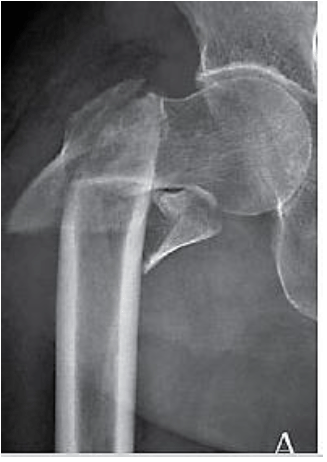

Classificamos a fratura abaixo como:

Provas